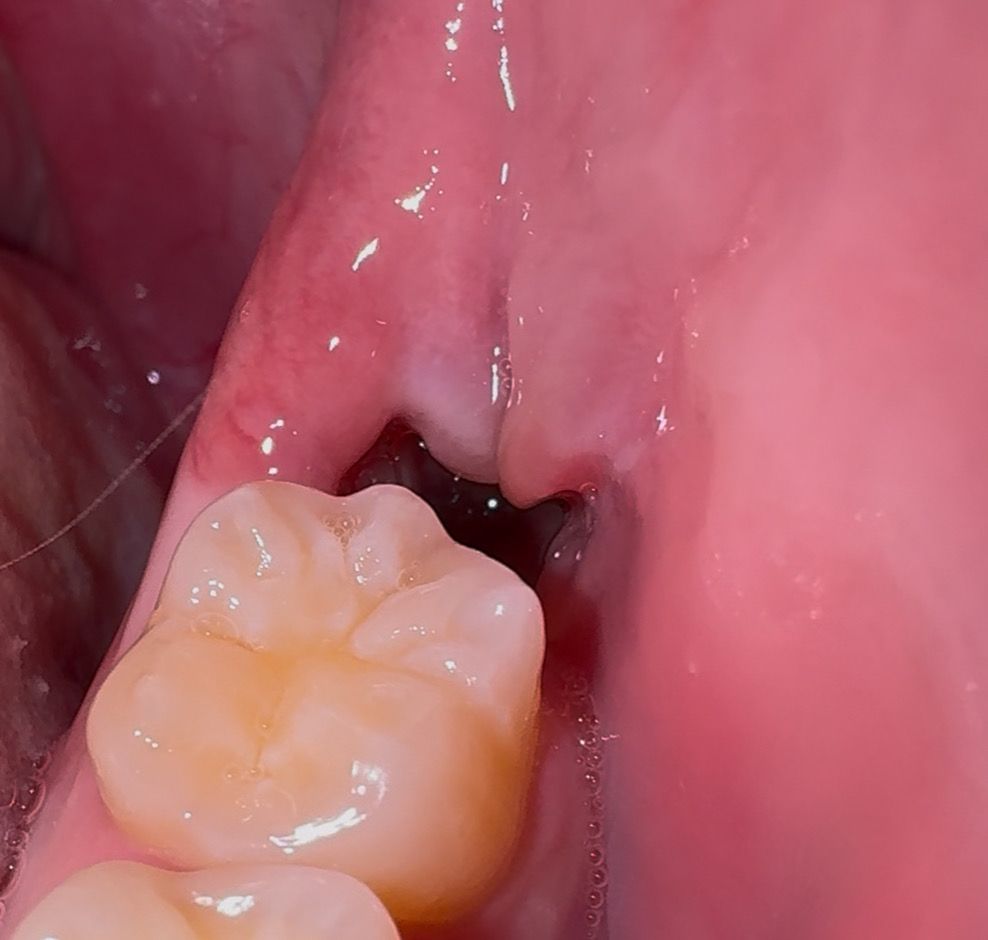

사랑니 발치 12일차, 잘 아물고 있을까요?

사랑니 뽑고 12일차입니다. 아물고있긴 한거같은데 저 튀어나온 살이 달랑거리는게 뭔가 굉장히 거슬리네요 ㅠㅠ 원래 이런건가요? 잘 아물고 있는걸까요?

• 1번 째 사진

사진 상으로는 특별히 이상이 보이진 않습니다. 완전히 아무는데에는 시간이 필요하니 천천히 기다리시면 됩니다.

발치한곳 잇몸이 다 아물지 않아서 그렇게 보이는거니 시간이 지나면잇몸이 아물면서 괜찮아 지실꺼에요.

시랑니를 발치하고 나면 잇몸이 올라와 있을수 있습니다 이런 부위는 대부분 시간이 지나면서 자연스럽게 아물게 됩니다.